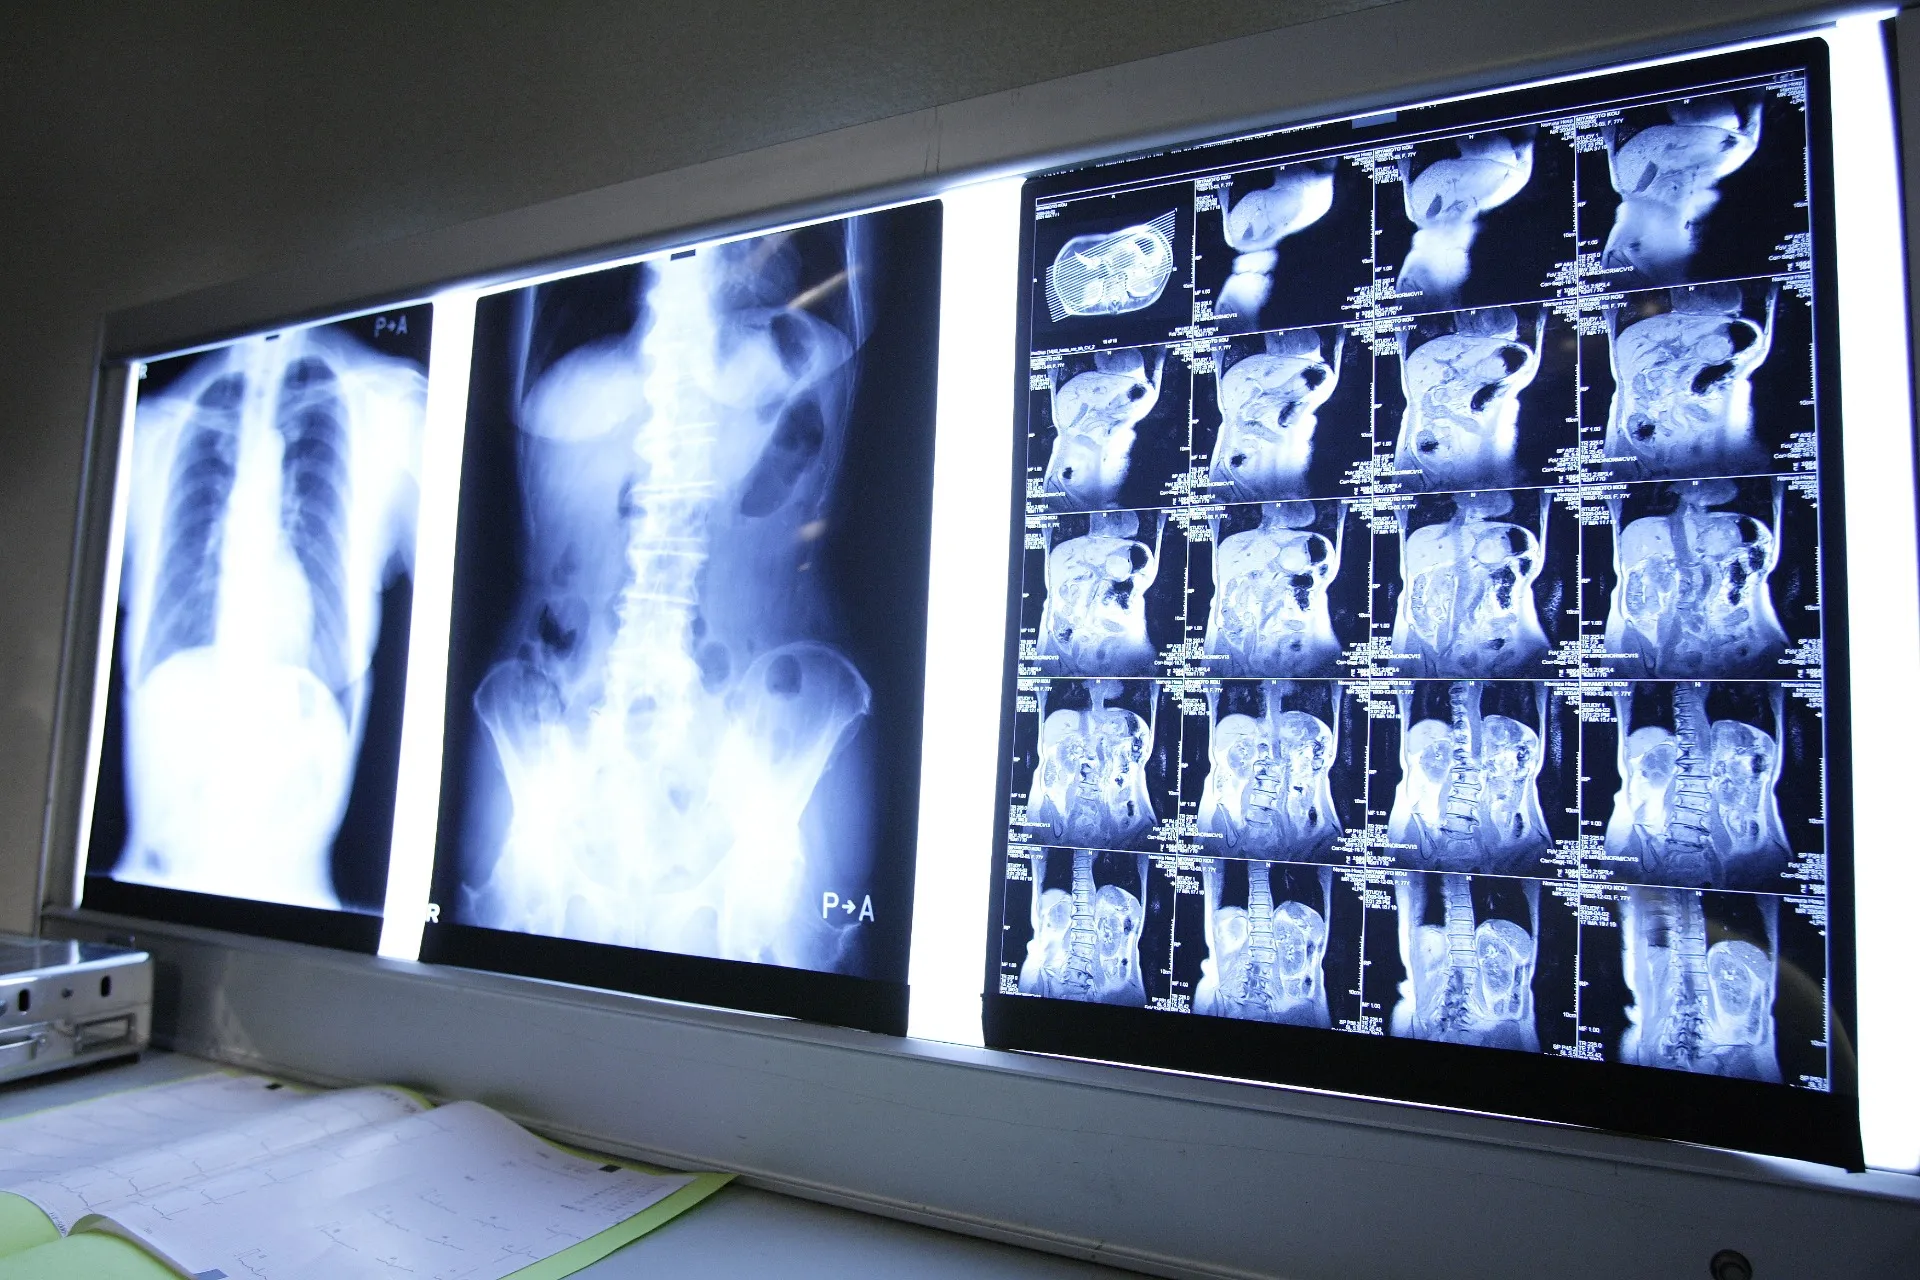

診断には身体の視診だけでなく、X線、CT、MRI、超音波検査、場合によっては血液検査なども行われます。